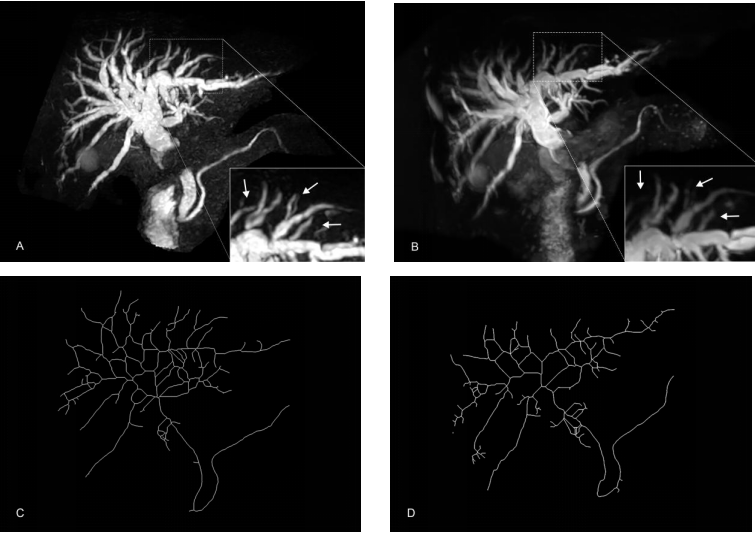

图1. 取自一名胆总管结石导致胆管扩张的受试者,5T(A)展示了比3T(B)更多的胆管树细节(白色箭头)。C、D是5T和3T下扩张的胆管树的骨骼化图。